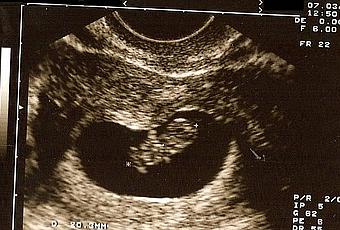

Y efectivamente, estaba embarazada. Esa raya se fue tiñiendo más y más y apenas unas semanas más tarde pudimos ver una gambita latiendo en mi interior.

Esta ecografía nos la hicimos estando de 8+5. Me encantó cómo le "retrararon" y estuvo mucho tiempo pegada en el frigorífico. De hecho, ha estado puesta hasta hace bien poco. Como no sabíamos si era niño o niña, nada más quedarnos embarazados decidimos dirigirnos a él como "embri" y así le estuvimos llamando bastante tiempo, hasta que finalmente elegimos su nombre (incluso tiempo después). Siempre que pasábamos por el frigorífico le dábamos un besito, a esta ecografía y a otras que fui poniendo.(Continuará...)